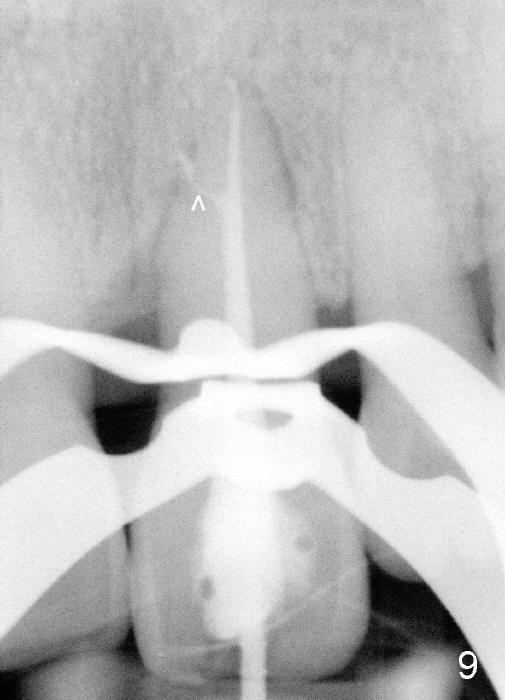

A 60-year-old lady had an abscess mesial to #9 six years ago (Fig.1,2 <), treated as a perio lesion by laser (Fig.3) and osseous surgery without bone graft (Fig.6, followed by CT exam revealing semi-circumferential bone loss (Fig.4,5). When the perio treatment failed, attention was paid to endo aspect (Fig.7-9). In fact the pulp was found to be vital when access to root canal therapy was made. As expected, the treatment failed again. The palatal fistula persisted. The infection was suspected to be a source of remote immediate implant site (#30). The tooth #9 was extracted. It appears that there is a semilunar crack line in the linguomesial root (Fig.12). When the socket healed 2 weeks post extraction (Fig.10), the #30 buccal defect was debrided with bone graft. There was no bone resorption 4 weeks post extraction (Fig.11); a 4.5x17 mm implant was placed (Fig.13-15). An immediate provisional was fabricated (Fig.16-18). Fig.19,20 were taken 3 months post implantation and 7 months post cementation, respectively. Dense bone forms around the implant coronally 4 years 5 months post cementation (Fig.21), while the gingiva is healthy palatally (Fig.22) and buccally (Fig.23).